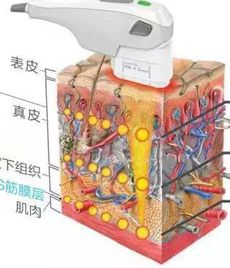

超声刀抗衰是什么原理,需要动刀吗?

超声刀不是刀,通过超音波能量深层穿透,直达皮肤SMAS层产生凝结点,令胶原蛋白新生重组,构建胶原蛋白纤维网,改善皮肤衰老问题。【了解详情】